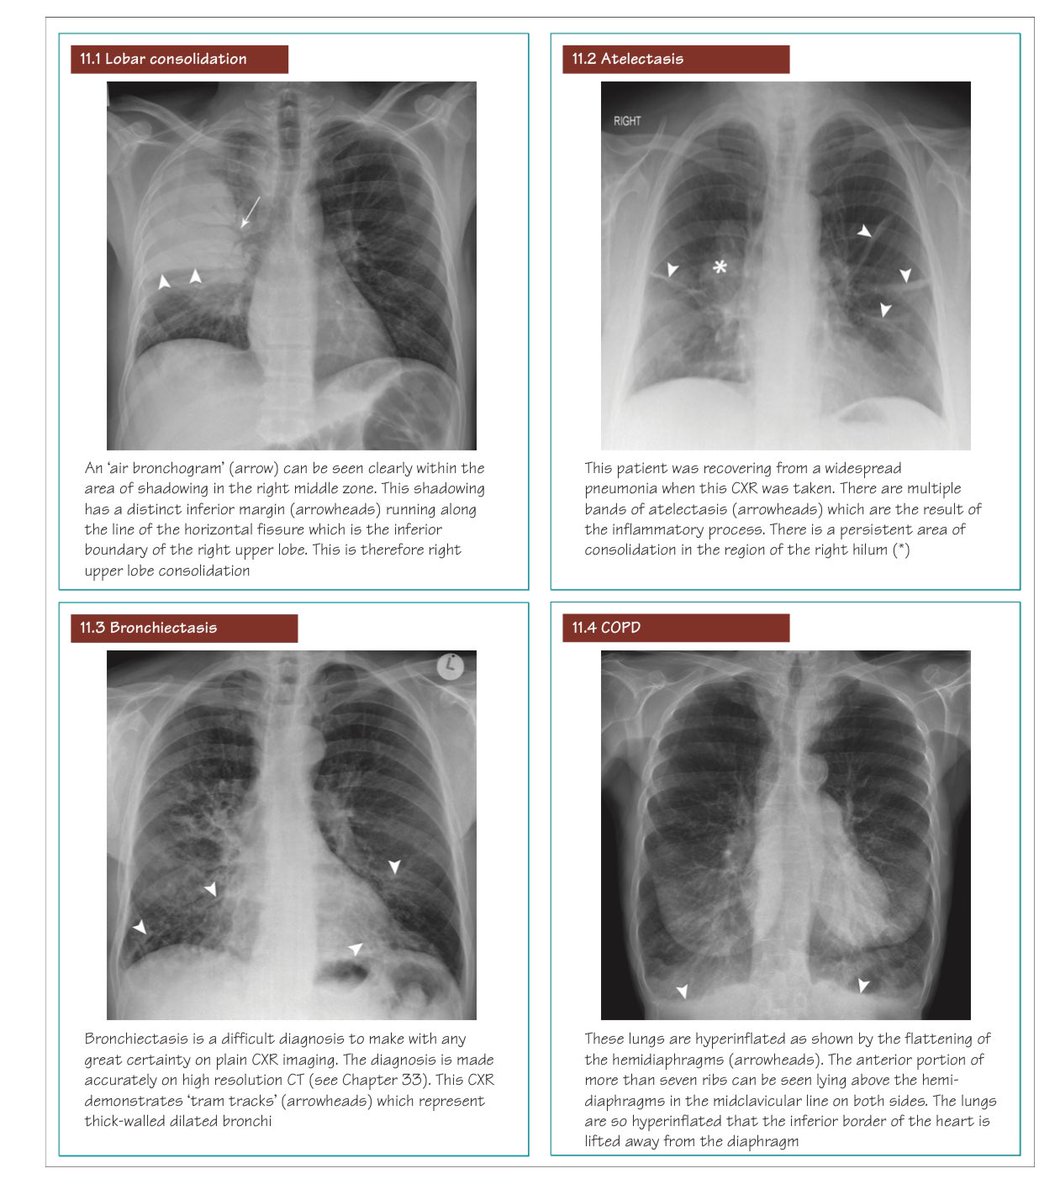

تصوير الصدر بالأشعة السينية من أول الإجراءات التي تخضع لها في حال اشتباه إصابتك بمرض في القلب أو الرئة لا سمح الله

هام جدا☢️

الأمراض الصدرية وكيفية تمييزها على صور الأشعة الأشعة السينية 👇🏼

CXR classic cases